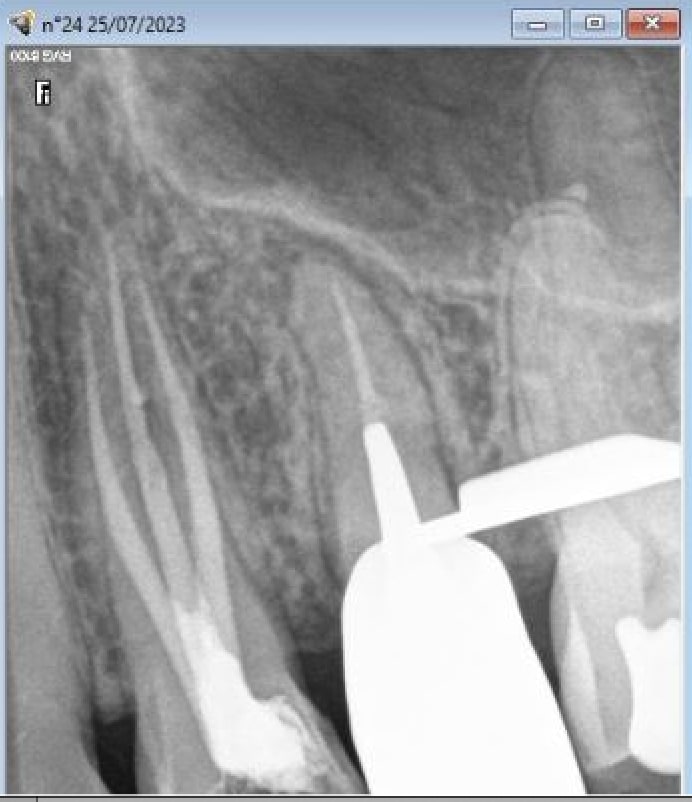

Je te trouve un peu dur dentarue ... heureusement que certains confrères bossent comme des gorets, sinon tu ferais quoi ? Ton cas 25 / 26, c'est 5 minutes pour déposer la 25, 20 minutes au max pour traiter la 25, et 5 minutes pour gicler la 26. Heureusement qu'il a pondu cette bouse le confrère, ça t'evite de faire une endo conventionnée, et poser au mieux 2 zi rac0 ;)

Souricette a fait un taf de ouf et je l’en félicite.

Elle a posé un bridge de 13 à 17 avec molaires en acier pour respecter le c2s. La cotation n’existe pas, mais c’est pas le sujet. Ah, on me dit que si, finalement c’est le sujet, ces putains de molaires en acier ! Que dire, je reste coi…

La patiente a mal, les endos pêchent peut être, chose qu’elle reconnait sans souci, la main sur le portefeuille. Quelle générosité !

Ses radios sont inattaquables, avant, en cours, après, tout est parfaitement documenté, qui pourrait douter ? QUI ?